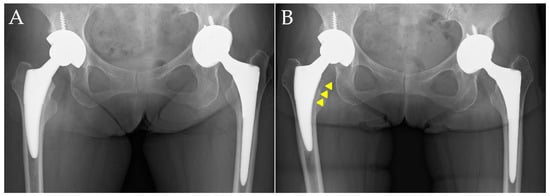

| Stress shielding (hips) | |||

| Grade 0 | 12 | 6 | 0.001 |

| Grade 1 | 10 | 28 | |

| Grade 2 | 12 | 46 | |

| Grade 3 | 2 | 11 | |

| Grade 4 | 0 | 3 | |